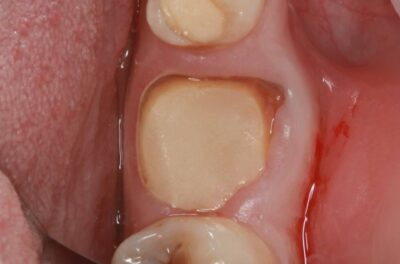

Специализация: терапия(эндодонтия), ортопедия, имплантология.